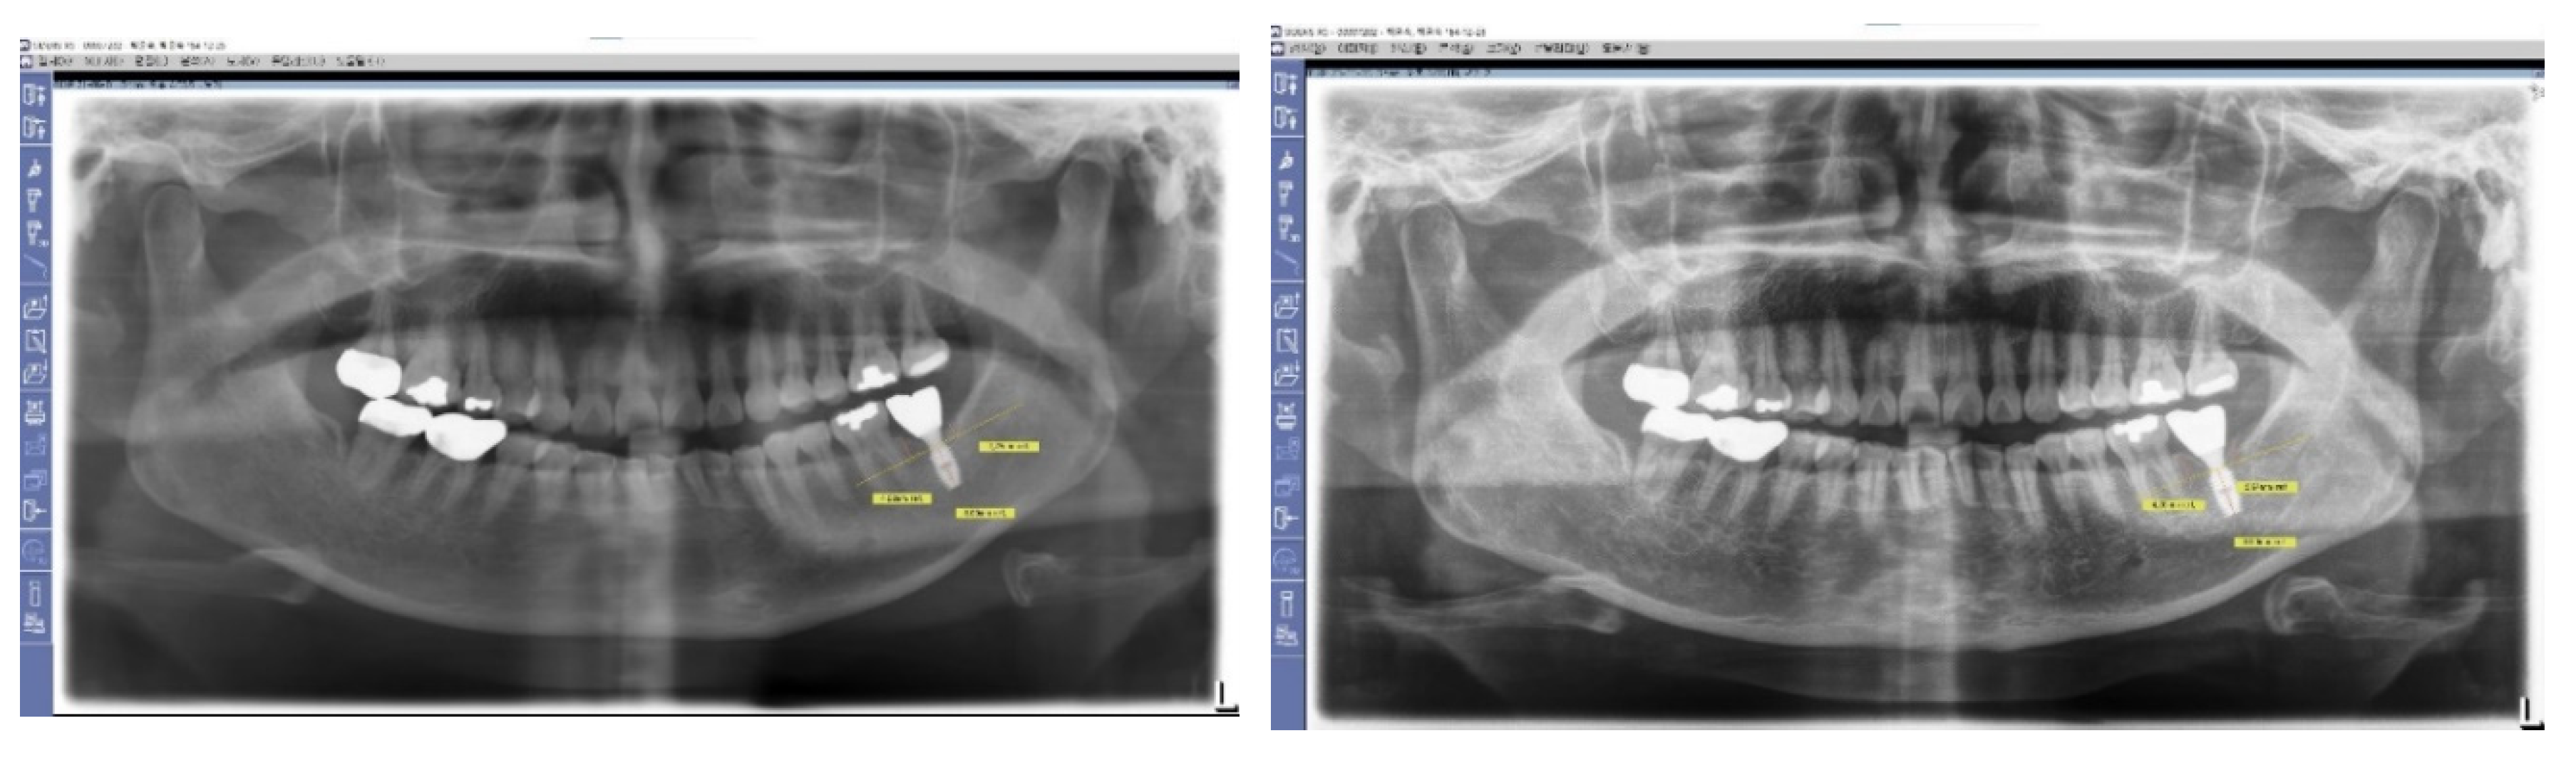

Figure 9. X-Ray Sequence of Healing Abutment Changes. This series of X-rays illustrates the procedural sequences for implant placement and subsequent adjustments. Initially, healing abutments measuring 5 mm in diameter and 2.5 mm in height were placed and covered with primary flap closure. After three months, a second operation was undertaken for the prosthetic procedure. During this stage, the sites were uncovered and longer healing abutments, maintaining the same profile as the initially embedded abutments, were connected to prepare for final prosthesis installation.

Preprints 103958 g009